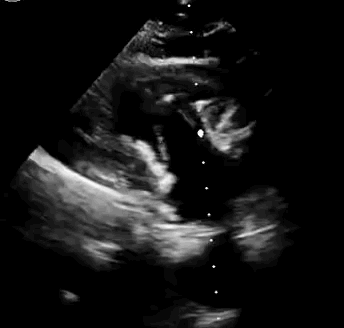

本次臨床前研究經(jīng)右側(cè)頸靜脈置入LuX-Valve Plus輸送系統(tǒng)可調(diào)彎鞘管,在DSA及超聲引導(dǎo)下將人工三尖瓣瓣膜植入到原有三尖瓣位置,利用獨(dú)特的錨定技術(shù)將人工瓣膜支架可靠固定在預(yù)定的位置。

上海中山醫(yī)院葛均波院士、錢菊英院長、周達(dá)新教授、潘文志教授、潘翠珍教授、李偉教授共同完成此次臨床前研究。術(shù)后葛均波院士對Lux-Valve Plus的器械操作性能給予了高度評價,DSA和超聲影像也顯示出在本次研究中Lux-Valve Plus的安全性和有效性俱佳。